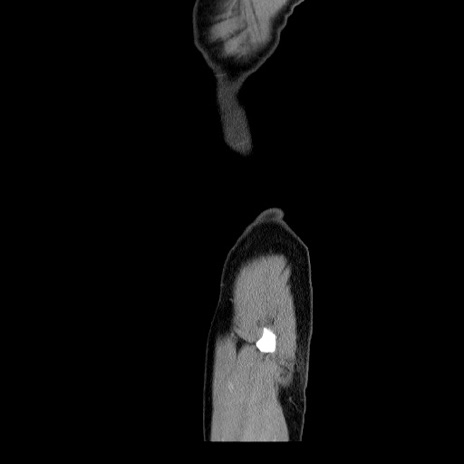

横断像